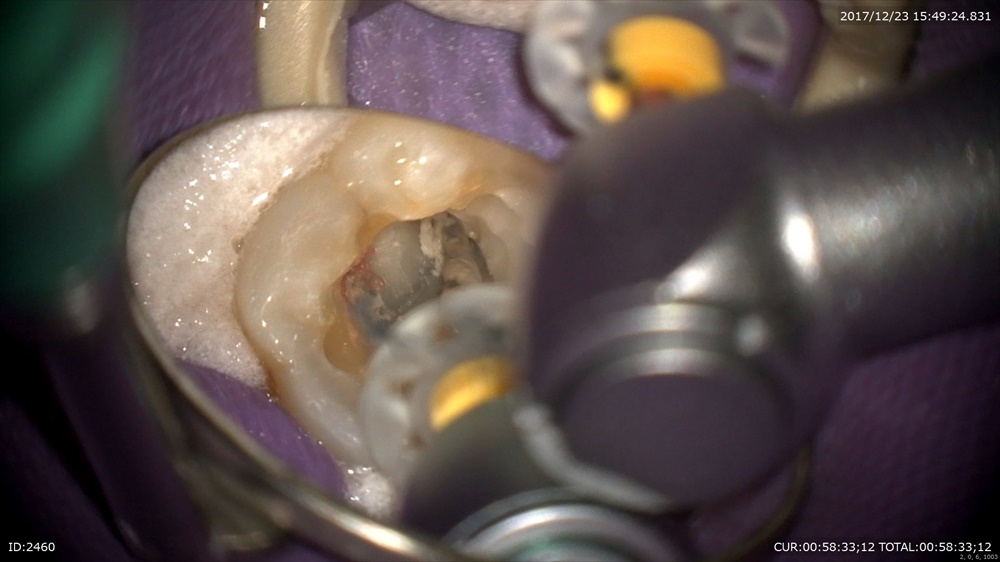

でもこんな重症でも精密根管治療。根管をしっかり見つけて

ストレートラインアクセスの為エンド三角を整理。

根管形成。汚れが出てくる出てくる。すべて使い捨ての器具で安心!!

イスムス

整理後綺麗になりました。1時間半の作業

Yさんこれでお正月大丈夫。